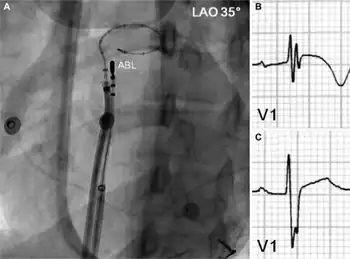

a) Deflectable ablation catheter and a 20-pole variable circular mapping catheter b) ECG before radiofrequency catheter ablation showed fragmented QRS complex c)fragmentation of QRS complex and T wave inversion disappeared after successful ablation